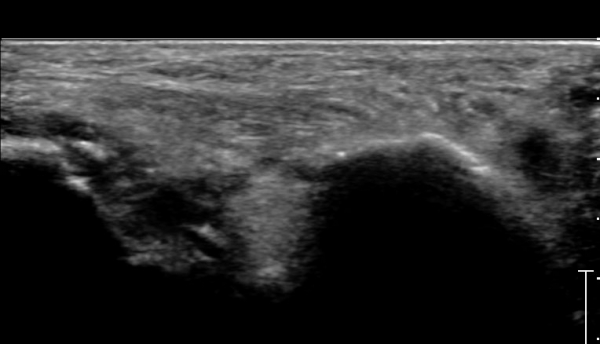

ÃÊÀ½ÆÄ°Ë»ç :  Àü°ÅºñÀδë Á¾´Ü¸é°Ë»ç¿¡¼­ Àü°ÅºñÀδëÀÇ Àú¿¡ÄÚ À§ÃàÀÌ °üÂûµÇ°í °Å°ñ °æºÎÀÇ °ß¿­°ñÀý ¹×

°Å°ñÁÖ»ó°ñ°üÀý ºÎÁ¾ÀÌ °üÂûµÈ´Ù(»çÁø 1).